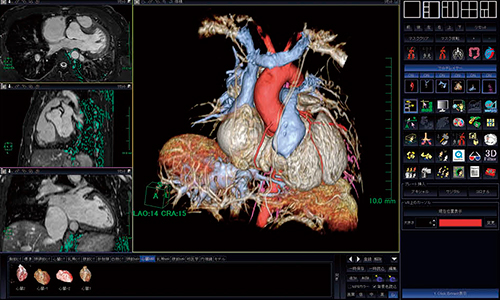

3.3D表示

3D whole heart MRA画像より,3Dソフトウェアを使用して,大血管や心房・心室の形態把握が容易に行える。3D構築を行う際には,マルチレイヤー機能を使用して色分けをすることにより,全体の血管走行や狭窄などの把握がよりわかりやすくなる(図4)。作成時間もソフトウェア内の数々のツールを使用することにより,短時間で行うことが可能となっている。

図4 3Dソフトウェアによる心・血管3D構築